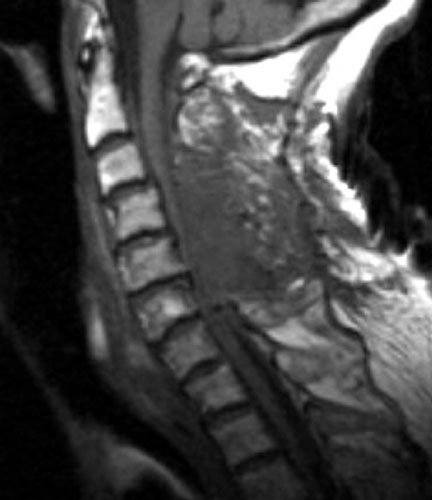

A B C

Non-enhanced sagittal T1 (A), sagittal T2 (B) and axial T1 images demonstrate a large fluid collection, predominantly low signal on T1, bright on T2 with a few areas of T1 hyperintesity mixed within. These constellation of findings are consistent with a post-operative epidural hematoma with blood products of various ages. There is severe severe spinal canal stenosis at C3-4, and very severe spinal canal stenosis at C4-5 and C5-6. The cord is markedly flattened in the anterior-posterior dimension, to approximately 2-3 mm secondary to mass effect from this fluid collection. There is abnormal T2 weighted hyperintensity within the substance of the cord at the C5-6 and C6-7 levels, consistent with some edema.